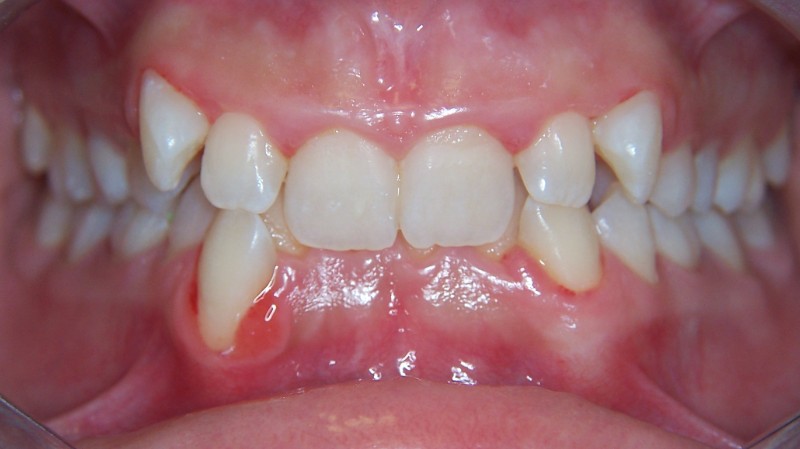

Prima e dopo il trattamento

Trascina il cursore per confrontare il risultato ottenuto.

Dopo il trattamento Prima del trattamento

Ortodonzia con mascherine trasparenti

Ortodonzia invisibile

Paziente: Donna, 17 anni